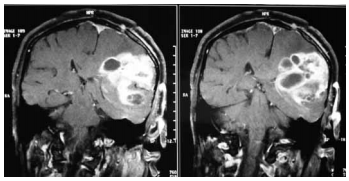

Uma mulher com cinquenta e três anos de idade foi admitida em um hospital apresentando, havia dois meses, quadro de cefaleia, hemiparesia à direita, náuseas e dificuldade na fala — todos de caráter progressivo. A paciente negou febre e não houve crise convulsiva nem alterações comportamentais. Os resultados do exame de ressonância magnética contrastada do crânio são mostrados na figura precedente. Com relação a esse caso clínico, julgue o item seguinte considerando o resultado das imagens. Deve-se iniciar o tratamento dessa paciente com anticonvulsivante profilático para se prevenir uma primeira convulsão.

Uma mulher com cinquenta e três anos de idade foi admitida em um hospital apresentando, havia dois meses, quadro de cefaleia, hemiparesia à direita, náuseas e dificuldade na fala — todos de caráter progressivo. A paciente negou febre e não houve crise convulsiva nem alterações comportamentais. Os resultados do exame de ressonância magnética contrastada do crânio são mostrados na figura precedente. Com relação a esse caso clínico, julgue o item seguinte considerando o resultado das imagens. No caso em questão, caso ocorram síncopes causadas por tosse, espirros ou por vômitos, elas refletirão reduções temporárias da pressão de perfusão cerebral, associadas a ondas platô — tipo A de Lundberg — na pressão intracraniana.

Uma mulher com cinquenta e três anos de idade foi admitida em um hospital apresentando, havia dois meses, quadro de cefaleia, hemiparesia à direita, náuseas e dificuldade na fala — todos de caráter progressivo. A paciente negou febre e não houve crise convulsiva nem alterações comportamentais. Os resultados do exame de ressonância magnética contrastada do crânio são mostrados na figura precedente. Com relação a esse caso clínico, julgue o item seguinte considerando o resultado das imagens. Os sintomas descritos no caso clínico podem ser reduzidos com a administração de dexametasona venosa em alta dose.

Uma mulher com cinquenta e três anos de idade foi admitida em um hospital apresentando, havia dois meses, quadro de cefaleia, hemiparesia à direita, náuseas e dificuldade na fala — todos de caráter progressivo. A paciente negou febre e não houve crise convulsiva nem alterações comportamentais. Os resultados do exame de ressonância magnética contrastada do crânio são mostrados na figura precedente. Com relação a esse caso clínico, julgue o item seguinte considerando o resultado das imagens. A espectroscopia por ressonância magnética nessa paciente evidenciará, no local da lesão, aumento de N-acetilaspartato e redução de colina.